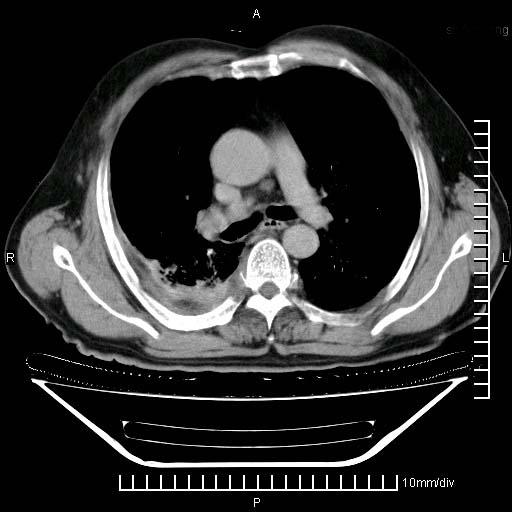

既往肺结核,近10几天,咳嗽,咳痰,右侧胸痛,疼痛较明显,右上肺斑块考虑结核灶胸膜粘连,增强,可惜动脉期没有定好,未见强化,可延迟4分后又见较明显强化,中心见低密度影,如果说结核是边缘强化,可这个灶强化的面积挺大的,让人很挠头。

肺癌能排除吗?

强化的组织可能是膨胀不全的肺组织或炎性肉芽组织。

1)两肺继发性肺结核。2)右侧胸膜增厚+少量胸腔积液。